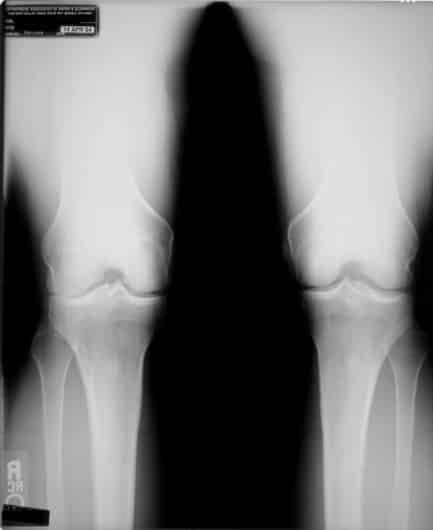

Zie hieronder een röntgenfoto voor een voorbeeld. Zoals u kunt zien is een deel van het kraakbeen van de rechterknie weggesleten (links op de foto). Hierdoor staat de knie naar binnen. Maar wat was er eerst, de slijtage van het bot of de stand van de knie?